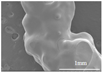

3.4. Microscopic Characterization of Tablet Structures

| Gel Ink | Print Temperature (°C) | Optical Microscopy | SEM | 3D Structure Evaluation | Appearance | Weight Variation (%) | |||

|---|---|---|---|---|---|---|---|---|---|

| Gel Ink | Gel Ink | Filament | Top | Side | Bottom | ||||

| F1 | 36 |  |  |  |  |  |  |  | ±8.1 |

| F2 | 37 |  |  |  |  |  |  |  | ±12.8 |

| F3 | 42 |  |  |  |  |  |  |  | ±8.0 |

| F4 | 38 |  |  |  |  |  |  |  | ±8.7 |

| F5 | 39 |  |  |  |  |  |  |  | ±3.1 |

| F6 | 40 |  |  |  |  |  |  |  | ±3.5 |

| F7 | 41 |  |  |  |  |  |  |  | ±3.3 |